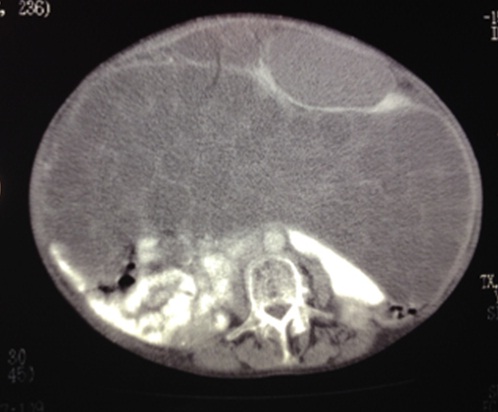

Las  imágenes de tórax no arrojaron datos de importancia y en abdomen  se ve desplazamiento posterior de ambos riñones y ásas intestinales, coherente  con síndrome compartimental, además de formaciones quísticas múltiples en  peritoneo.

Imagen 1. Se aprecia  desplazamiento de asas intestinales y ambos riñones en sentido dorsal

Imagen 2. Se observa  con más claridad las imágenes quísticas diseminadas